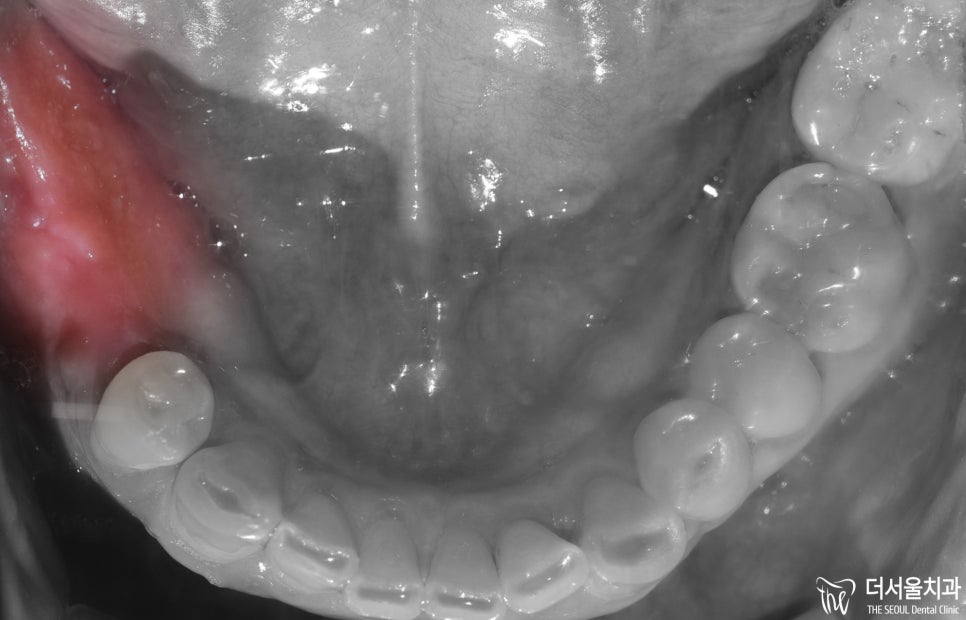

아래턱을 살펴보면

오른쪽 부위를 상실하였으며

골폭이 줄어든 것을 확인할 수 있었습니다.

오랫동안 치료받지 않고

방치한 만큼

구강 상태가 좋지 못했습니다.